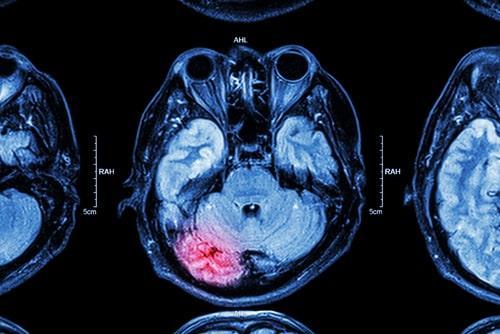

A traumatic brain injury occurs when an external force causes damage to the brain. This can happen for many reasons, including car accidents, sports injuries, falls, or even physical assault. Today, we will discuss the wide-ranging symptoms and effects of such injuries and the legal remedies available for someone who suffers this type of injury. If you have suffered a TBI and are wondering what legal options you may have, contact a personal injury attorney who will ensure that your rights remain protected and respected and that a positive case outcome can be pursued in your favor.

The extent to which someone is injured can play a significant role in the symptoms they experience. For example, if someone experiences a mild TBI, symptoms may include headaches, confusion, dizziness, and fatigue. However, more severe TBIs can lead to loss of consciousness, seizures, paralysis, and even death. TBI can have long-lasting and life-altering effects. In severe cases, individuals may experience various physical, cognitive, and emotional changes. These can include difficulty with balance and coordination, speech and language difficulties, memory and concentration problems, and changes in mood and behavior.